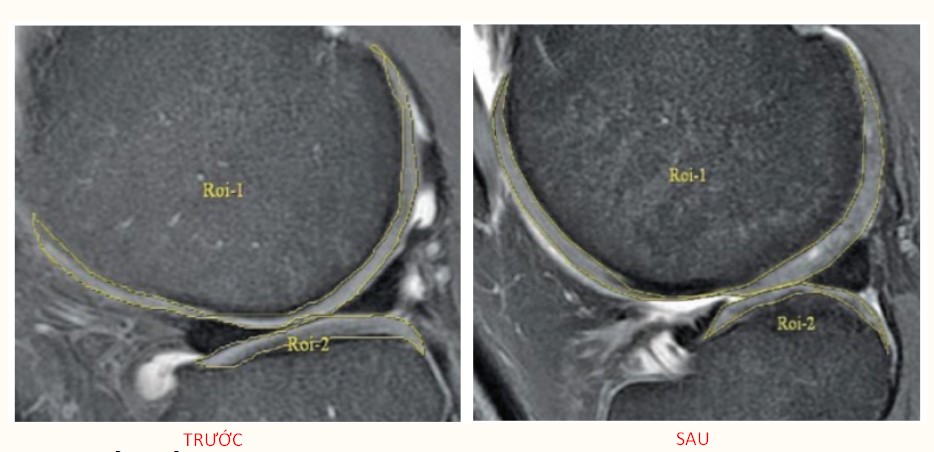

Dùng cho trị liệu khớp gối:

Tiêm exosome vào khớp gối bằng cách đưa exosome vào vùng bị tổn thương. Chúng kích thích sản xuất các yếu tố tăng trưởng hỗ trợ sửa chữa mô và tế bào sụn. Quá trình này giúp thay thế sụn bị mất và cải thiện chức năng khớp, giảm đau và viêm